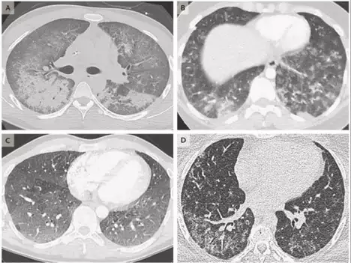

Junaid Khan, heart and lung surgeon at an Oakland hospital recently did a lung surgery on a man suffering from the blistered lung.

He released a scanned image of his lung and showcased that the there is a vent through which the air leaks between chest wall and lung that eventually let the blisters inside the lung.

Junaid further added that this could soon become a public health crisis if not appropriately addressed at the right time. He also stated the symptoms related to vaping illness. These mainly include fever, nausea, weight loss, shortness of breath, gastrointestinal issues, etc.